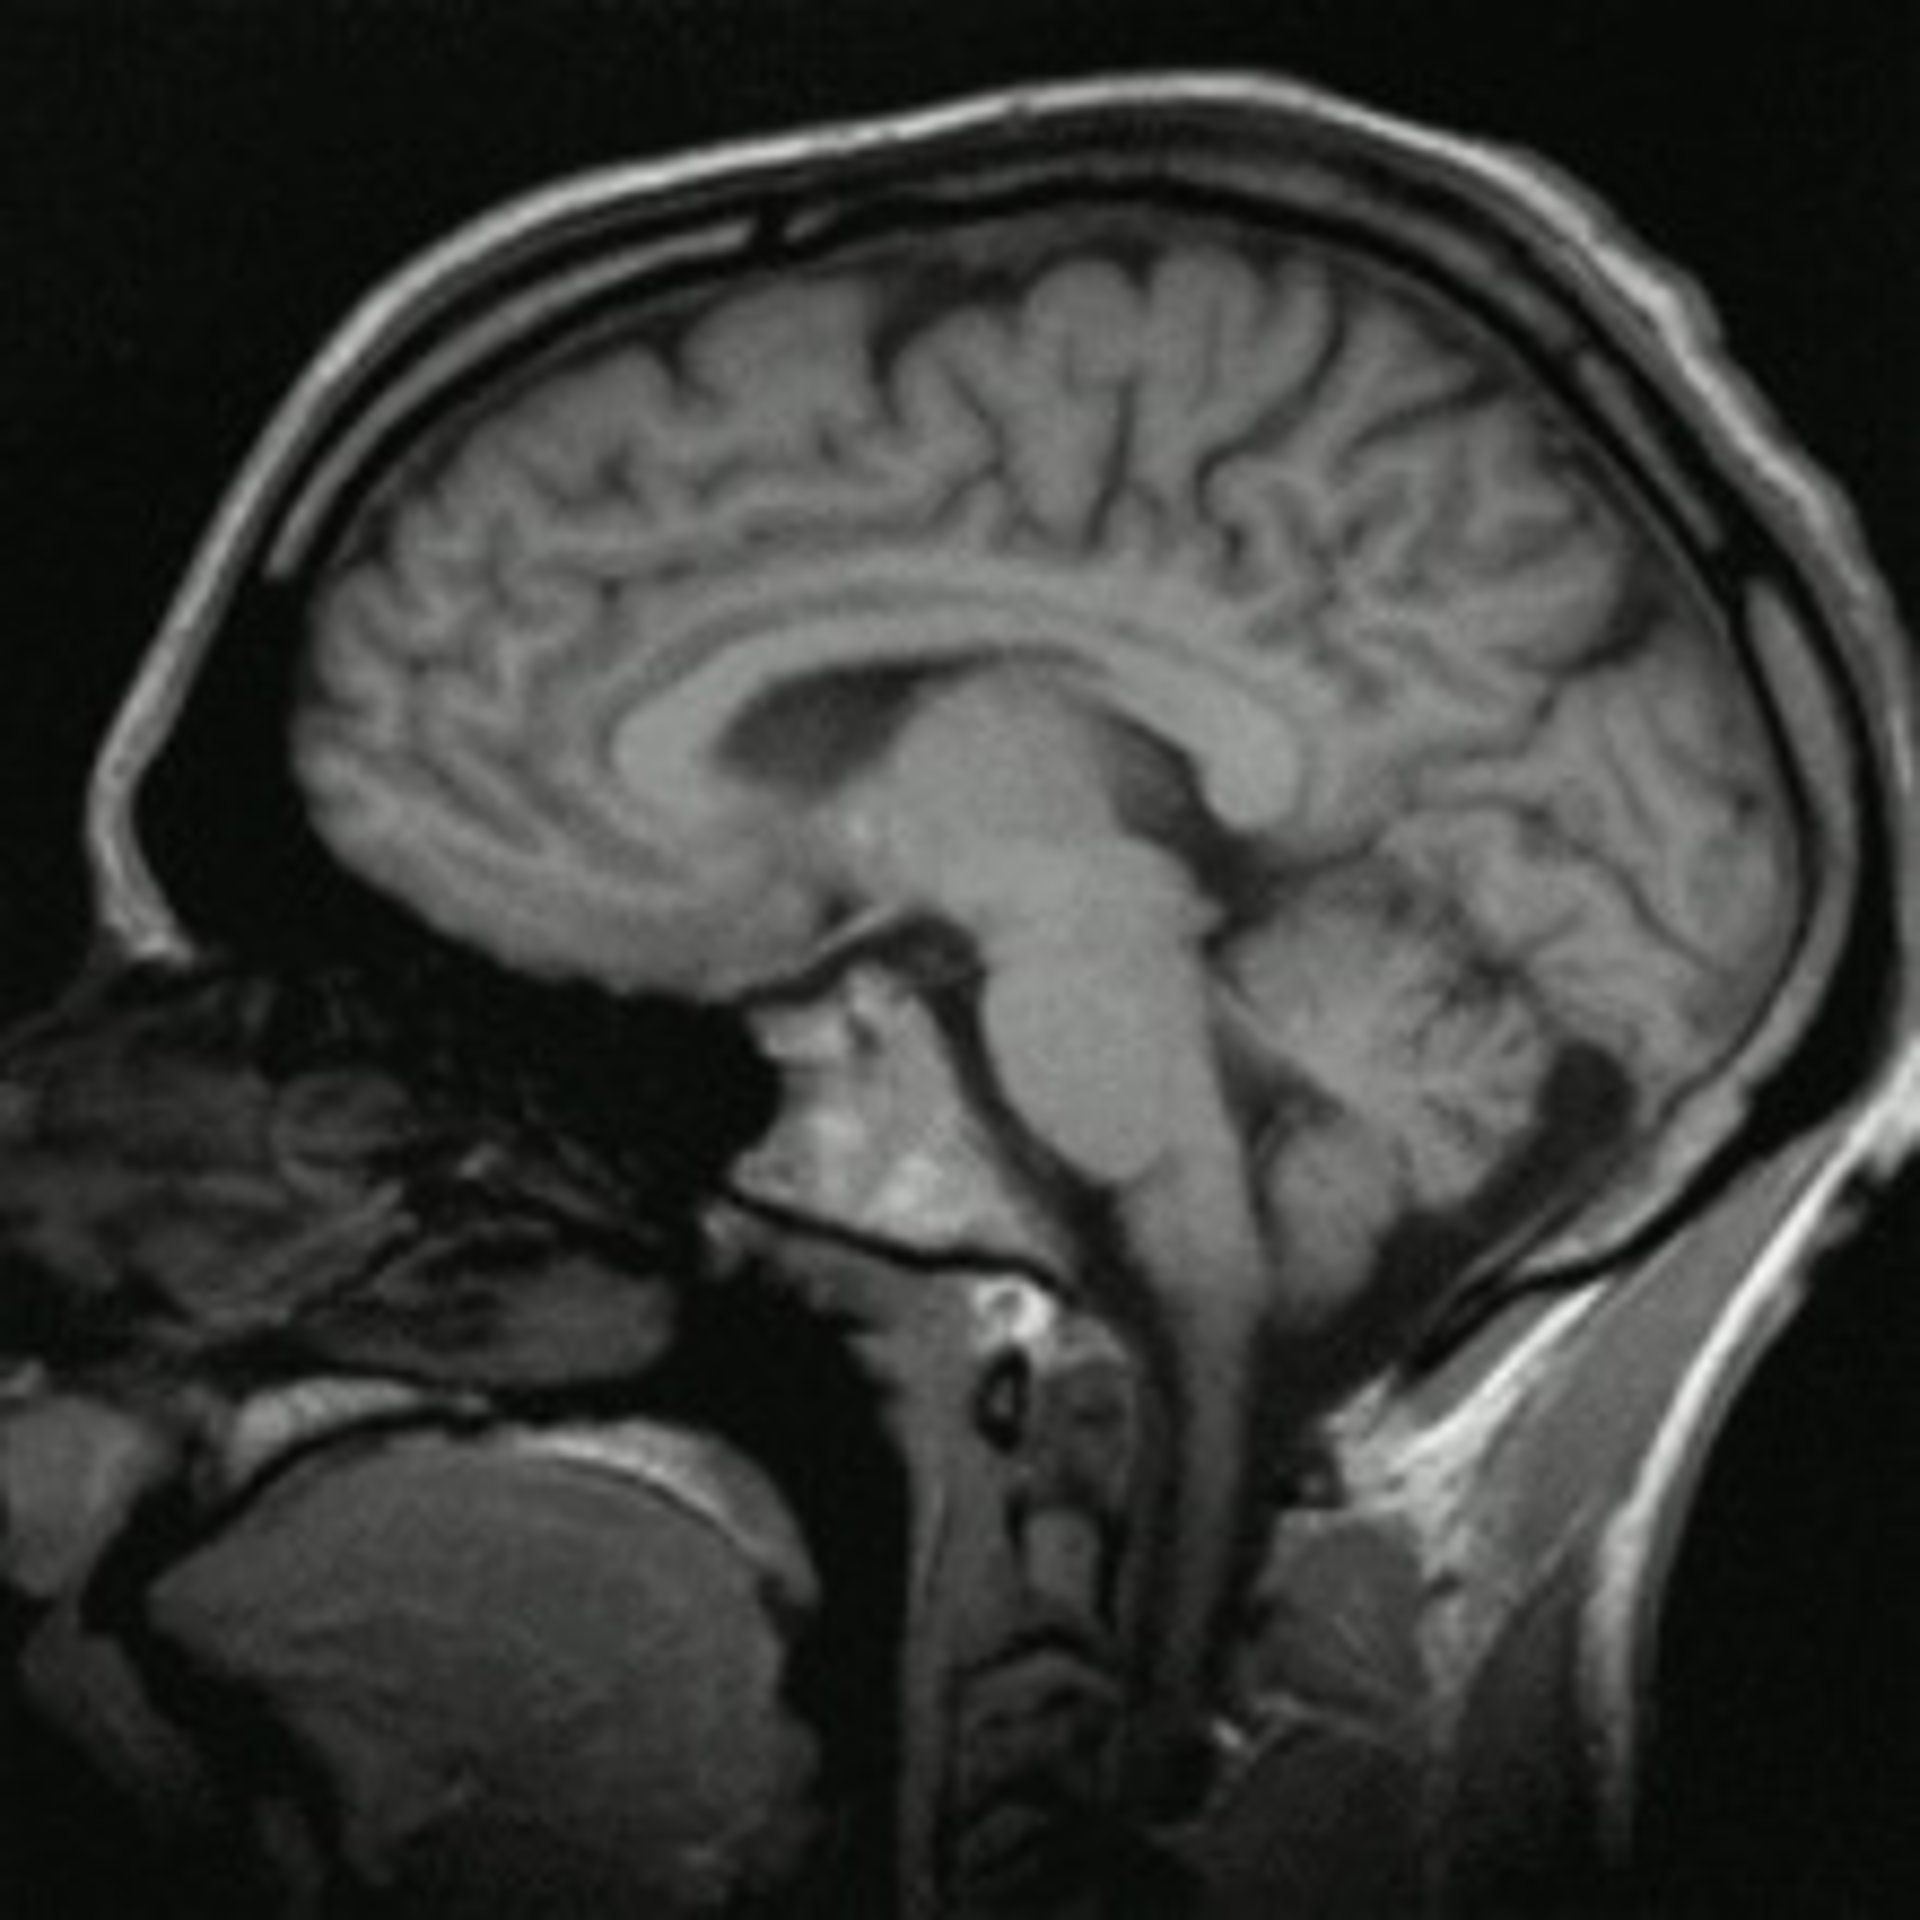

Para el estudio, los investigadores del Hospital McLean, en Massachusetts y un equipo de la Universidad de Utah emplearon imágenes por resonancia magnética (IRM) preparadas para detectar patrones microscópicos en las conexiones cerebrales. La prueba detectó en un 94 por ciento de los casos una forma de autismo.

El equipo realizó controles de este tipo en los cerebros de 30 personas con autismo y otras 30 personas sin la condición. Así, hallaron que el circuito cerebral es muy diferente en quienes padecen autismo, comparado con las personas con un funcionamiento cerebral normal, especialmente en zonas del cerebro relacionadas con el lenguaje y la función social y emocional.

A través del análisis de seis aspectos del circuito cerebral, el test pudo detectar correctamente a las personas diagnosticadas con autismo con un 94 por ciento de exactitud. Un nuevo estudio con dos grupos diferentes de participantes mostró el mismo nivel de alta precisión.